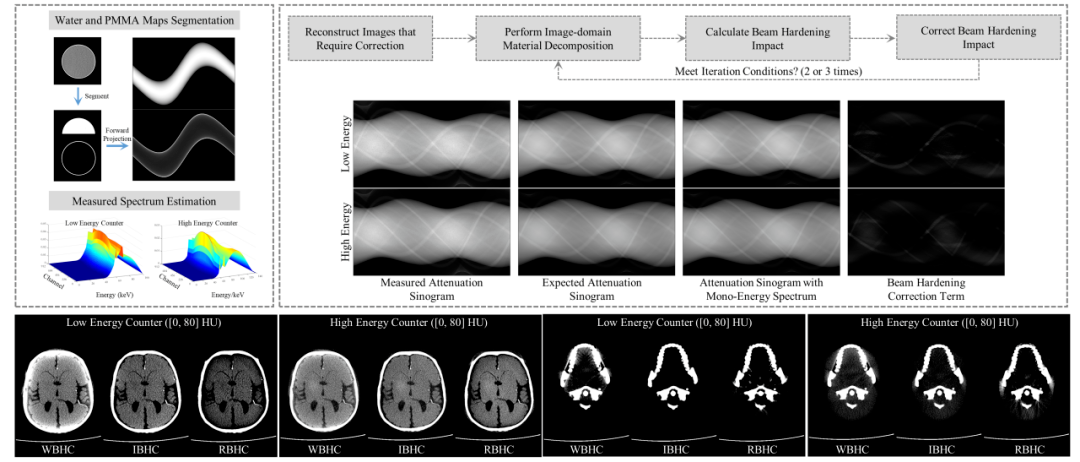

3. 探测器能谱驱动的射束硬化校正:课题组硕士研究生范涛和博士研究生秦文辉等人在《IEEE Transactions on Radiation and Plasma Medical Sciences (IEEE TRPMS)》发表研究,提出了一种专门针对 PCCT 图像域物质分解的射束硬化校正 (IBHC) 方法。该方法利用高低能投影数据估算 X 射线测量光谱,计算并校正射束硬化效应引起的投影误差。实验表明,该方法能有效解决高密度骨骼周边的射束硬化伪影问题,显著提高了图像域材料分解的准确性。

图4:探测器能谱驱动的射束硬化校正算法流程图及校正结果